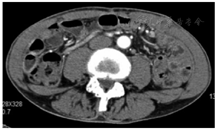

5例均在术前行腹部增强CT和MR排除腹腔及远处转移后行手术切除,术后恢复良好,无切口感染和切口疝发生。腹腔镜胃癌根治术大多采用"五孔法",各个穿刺孔都有可能发生种植转移。肿瘤位于皮下组织2例、肌层1例、脐部穿刺孔处2例(图1,图2,图3)。